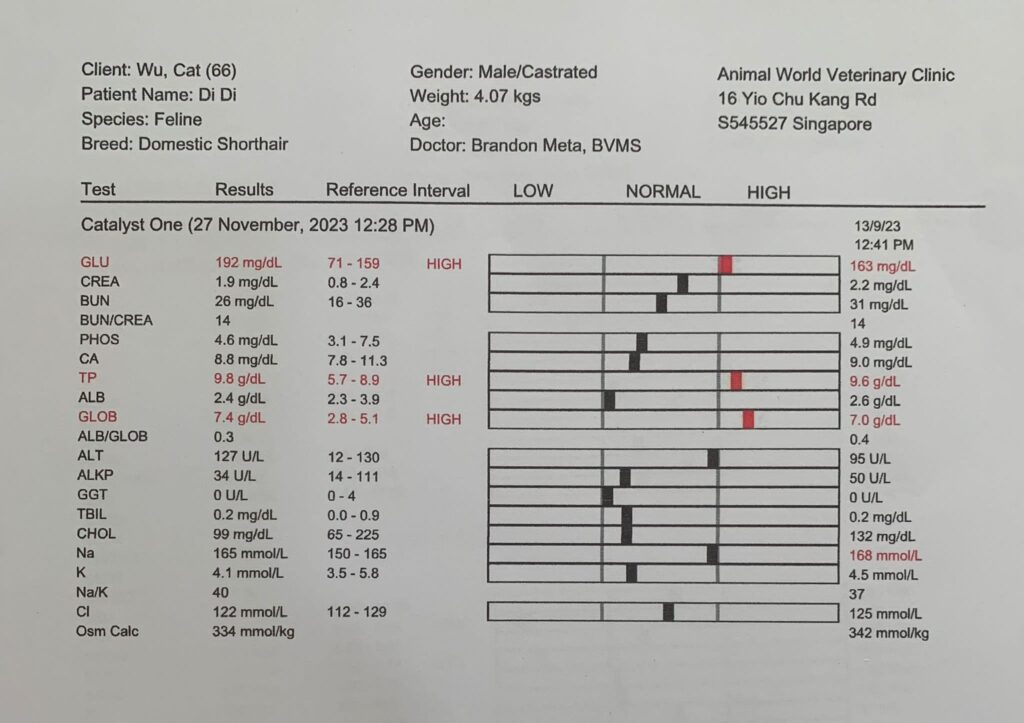

27 Nov 2023

1150am: see dr Brandon

4.07kg – lose 280g in 50 Days

Hct kidneys liver lytes all ok. Only glob and glu higher most prob due to stress/ mouth. Nothing else I can do. Exactly why I know didi is under the category of no need to see vet cos nothing significant can be found n done. Have to whack more money on bupre. dr told me to try im for better absorption. He tried open his mouth – fail badly. Too pain.

I think I need to recheck his glucose. But for now his lytes ok I’ll continue Subcut.